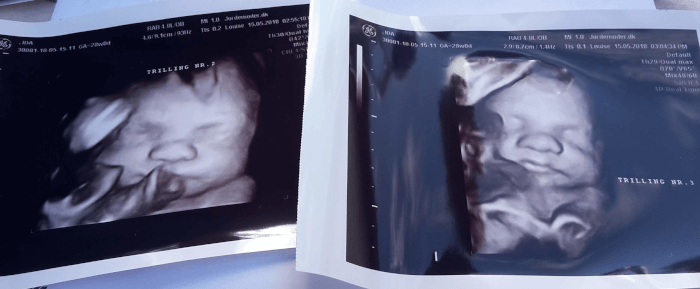

Den 16. maj 2018 havde jeg endnu en af de mange kontrolscanninger, som følger med en tvillingegraviditet. Endnu en dag hvor børnene skulle passes, for at vi kunne tage til Odense og endnu en gang få at vide at alt så fint ud.

Trillingerne havde det godt i maven og havde fine størrelser – alle tre var inden for normalen, så det kunne jo ikke være bedre. Min livmoderhals var de også begyndt at måle jævnligt (fordi en forkortet livmoderhals kan være tegn på for tidlig fødsel) og den så også fin ud med 4,8 cm.

Vi aftalte så at fra nu af skulle jeg komme til scanning hver 2. uge i stedet for hver 4. og så næste gang måtte vi hellere snakke om det der lungemodner.

Lungemodner er binyrebarkhormon, som gives for at modne baby’s lunger tidligere end normal, og er altså med til at give en for tidlig født baby bedre muligheder for at trække vejret.

Jeg var egentlig fast besluttet på at det skulle jeg ikke have, for både vi selv og lægen var jo overbeviste om at vores trillinger ville komme til verden ved planlagt kejsersnit i uge 36, og der ville det her lungemodner slet ikke være gavnligt.